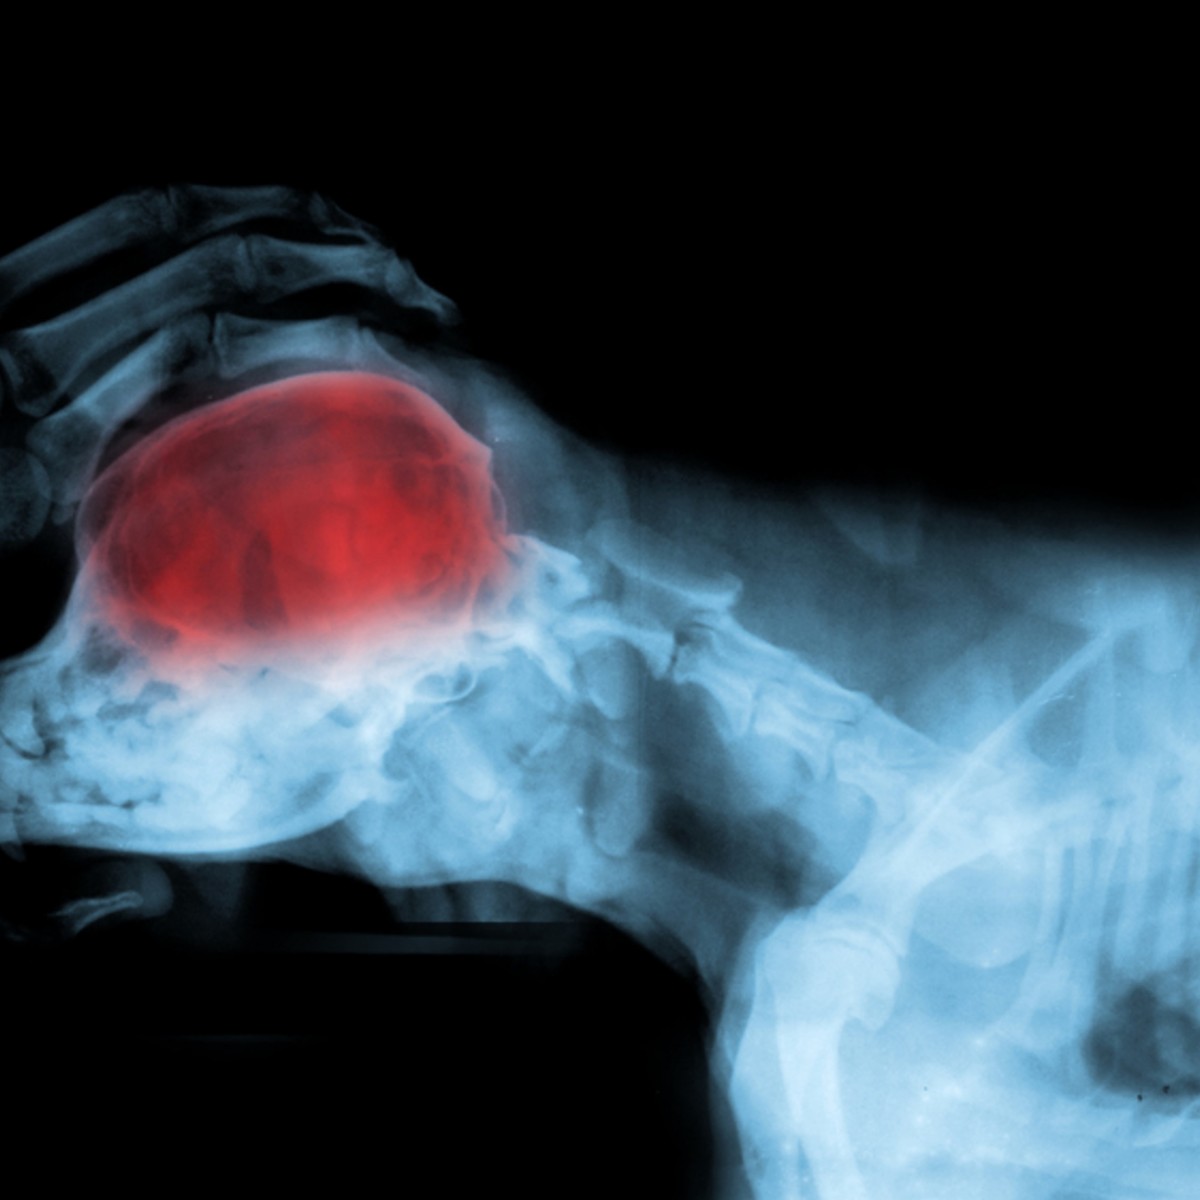

Canine brain tumours: a model for the human disease?

Canine brain tumours are becoming established as naturally occurring models of disease to advance diagnostic and therapeutic understanding successfully.

The size and structure of the dog's brain, histopathology and molecular characteristics of canine brain tumours, as well as the presence of an intact immune system, all support the potential success of this model.

The limited success of current therapeutic regimens such as surgery and radiation for dogs with intracranial tumours means that there can be tremendous mutual benefit from collaboration with our human counterparts resulting in the development of new treatments. The similarities and differences between the canine and human diseases are described in this article, emphasizing both the importance and limitations of canines in brain tumour research.